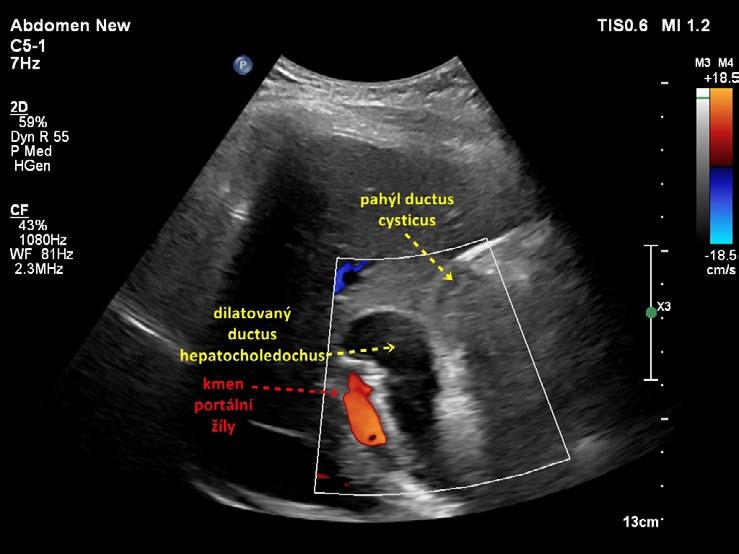

Příležitostně můžeme u pacientů po cholecystektomii zobrazit tenký pahýl ductus cysticus v délce několika milimetrů až 3 cm. Zvláště po laparoskopické cholecystektomii může být celý ductus cysticus nebo jeho fragment ponechán (obr. 1.21, obr. 1.22).

Obr. 1.21 Pahýl ductus cysticus po cholecystektomii

Obr. 1.22 Pahýl ductus cysticus po cholecystektomii